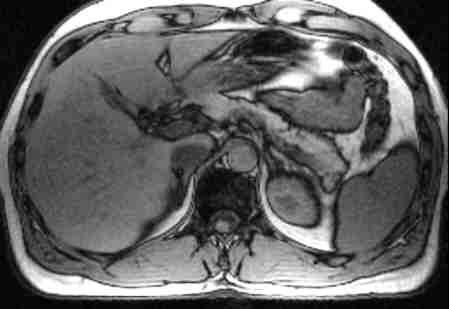

"Bei Leber lieber MRT !"

MRT Oberbauch

So lautete kürzlich das Urteil einer Expertenrunde. In zeitgemäßer Technik durchgeführt stellt die MRT derzeit das beste Verfahren dar, gutartige oder bösartige Leberherde darzustellen und zu unterscheiden. Dazu stehen heute verschiedene Kontrastmittel bereit, die eine besonders treffsichere Diagnostik ermöglichen.